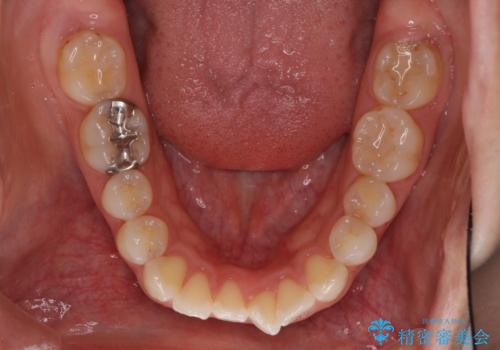

インビザラインにて抜歯矯正を行うと、高頻度で奥歯が咬み合わなくなります。

抜歯スペースが閉じてからも咬みにくさ改善のためマウスピース矯正を継続するため、治療期間は長期化します。